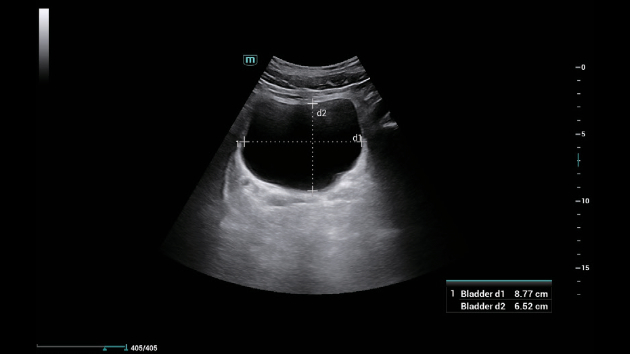

Smart Bladder: инновационная технология ультразвукового измерения объема мочевого пузыря

Технология Smart Bladder в ультразвуковых системах Mindray, таких как Consona N6 и N9, автоматизирует измерение объема мочевого пузыря, используя алгоритмы на основе эхографии. Она определяет три диаметра органа (продольный, поперечный и передне-задний) и вычисляет объем по встроенным формулам, что исключает ручные расчеты и минимизирует человеческие ошибки. Это особенно полезно в урологии и экстренной медицине, где необходимо быстро оценить задержку мочи или определить необходимость катетеризации. Для врачей это означает сокращение времени на процедуру и повышение точности диагностики, а для клиник — стандартизацию протоколов и снижение нагрузки на персонал.